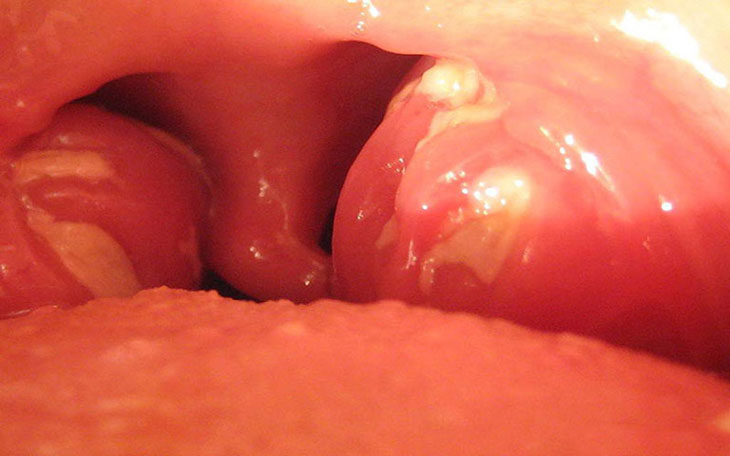

cac loai viêm amidan Hình ảnh Amidan bị viêm

• Xuất hiện các chấm mủ trắng hoặc vàng trên Amidan;

• Bề mặt Amidan có thể có màu đỏ tươi hoặc có lớp phủ (dịch tiết) màu trắng xám;

là tình trạng Amidan bị nhiễm trùng dai dẳng. Nhiễm trùng lặp đi lặp lại có thể gây ra sự hình thành các túi nhỏ trong Amidan là nơi chứa vi khuẩn. Thông thường sẽ phát triển những viên sỏi nhỏ (gọi là sỏi Amidan) có mùi hôi bên trong và ​​gây hôi miệng, vướng mắc phía sau cổ họng.